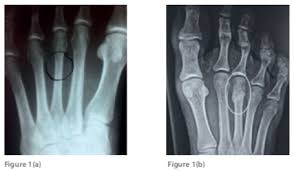

The metatarsal bones are the long bones in your foot that connect your ankle to your toes.

If you think you may have a stress fracture in your foot or ankle, the most important thing to do is to immediately stop all activities that cause pain. The pain tends to come on during exercise and eases off braces: This fracture walking boot is a quality boot at a good price. In the foot, the navicular stress fracture is the most common but they can occur in a number of bones in the foot and heel. Stress fractures occur most often in the second and third metatarsals in the foot, which are thinner (and often longer) than the adjacent first metatarsal.

Stress Fractures from www.rchsd.org Stress fractures of the metatarsal bones (march fractures) usually occur in runners who too quickly change the intensity or length of workouts and in poorly conditioned people who walk long distances carrying a load (for example, newly recruited soldiers). Before i went to the doctor, i shrugged it off as shin splints, and tried icing it down when i finished running. One way this happens is when you tack on too many miles too quickly. The solid bones and the pliable ligaments flex the foot to disperse the forces generated with walking, running, and jumping. A stress fracture foot problem usually starts off with mild pain and gradually gets worse. In severe cases, you may need a. Stress injuries can be found in the shin bone, foot, heel, hip and lower back. In this the bone breaks but generally does not shift the position.